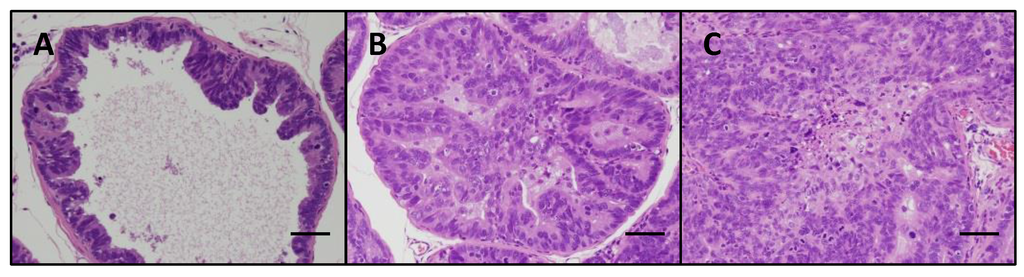

2.2. Assessment of Prostate Neoplastic Lesion Development

3.1. FBRA Suppressed Progression of Prostate Carcinogenesis without Toxicity